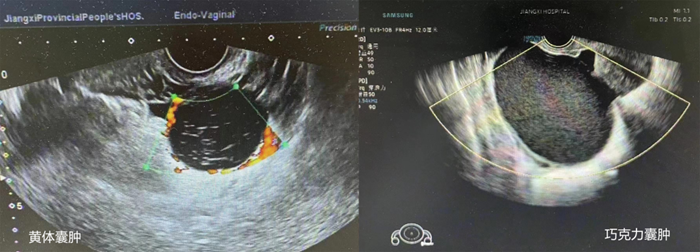

超声显示囊肿内含密集点状回声时,首先考虑为出血性囊肿(如黄体囊肿及子宫内膜异位囊肿等)。

超声显示卵巢囊肿内含密集点状回声伴实性强回声成分时,多为卵巢畸胎瘤,超声诊断的敏感度为58%,特异度为99%。